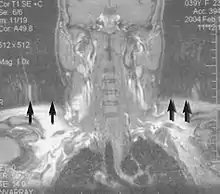

Musculoskeletal

Applications in the musculoskeletal system include spinal imaging, assessment of joint disease, and soft tissue tumors.[38] Also, MRI techniques can be used for diagnostic imaging of systemic muscle diseases including genetic muscle diseases.[39][40]

Swallowing movement of throat and oesophagus can cause motion artifact over the imaged spine. Therefore, a saturation pulse applied over this region the throat and oesophagus can help to avoid this artifact. Motion artifact arising due to pumping of the heart can be reduced by timing the MRI pulse according to heart cycles.[41] Blood vessels flow artifacts can be reduced by applying saturation pulses above and below the region of interest.[42]